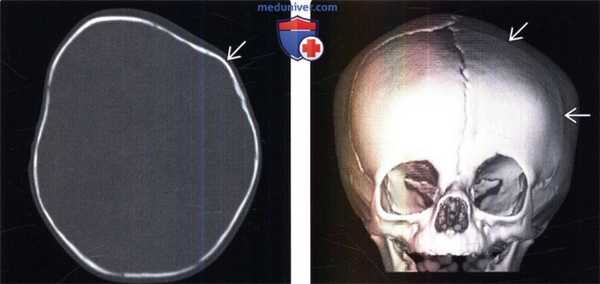

(Слева) КТ свода черепа, костное окно, аксиальный срез: у пациента, поступившего в лечебное учреждение с выраженной скафоцефалией, определяется сагиттальный синостоз. Обратите внимание на выпрямление и сужение сагиттального шва с выраженными гребнями. По ходу сагиттального шва визуализируются костные мостики и костное сращение.

(Справа) КТ, костный режим, сагиттальная 3D-реконструкция свода черепа: у этого же пациент наблюдаются заметная долихоцефалия и характерные признаки изолированного сагиттального синостоза. Венечный, лямбдовидный и чешуйчатый швы в норме.